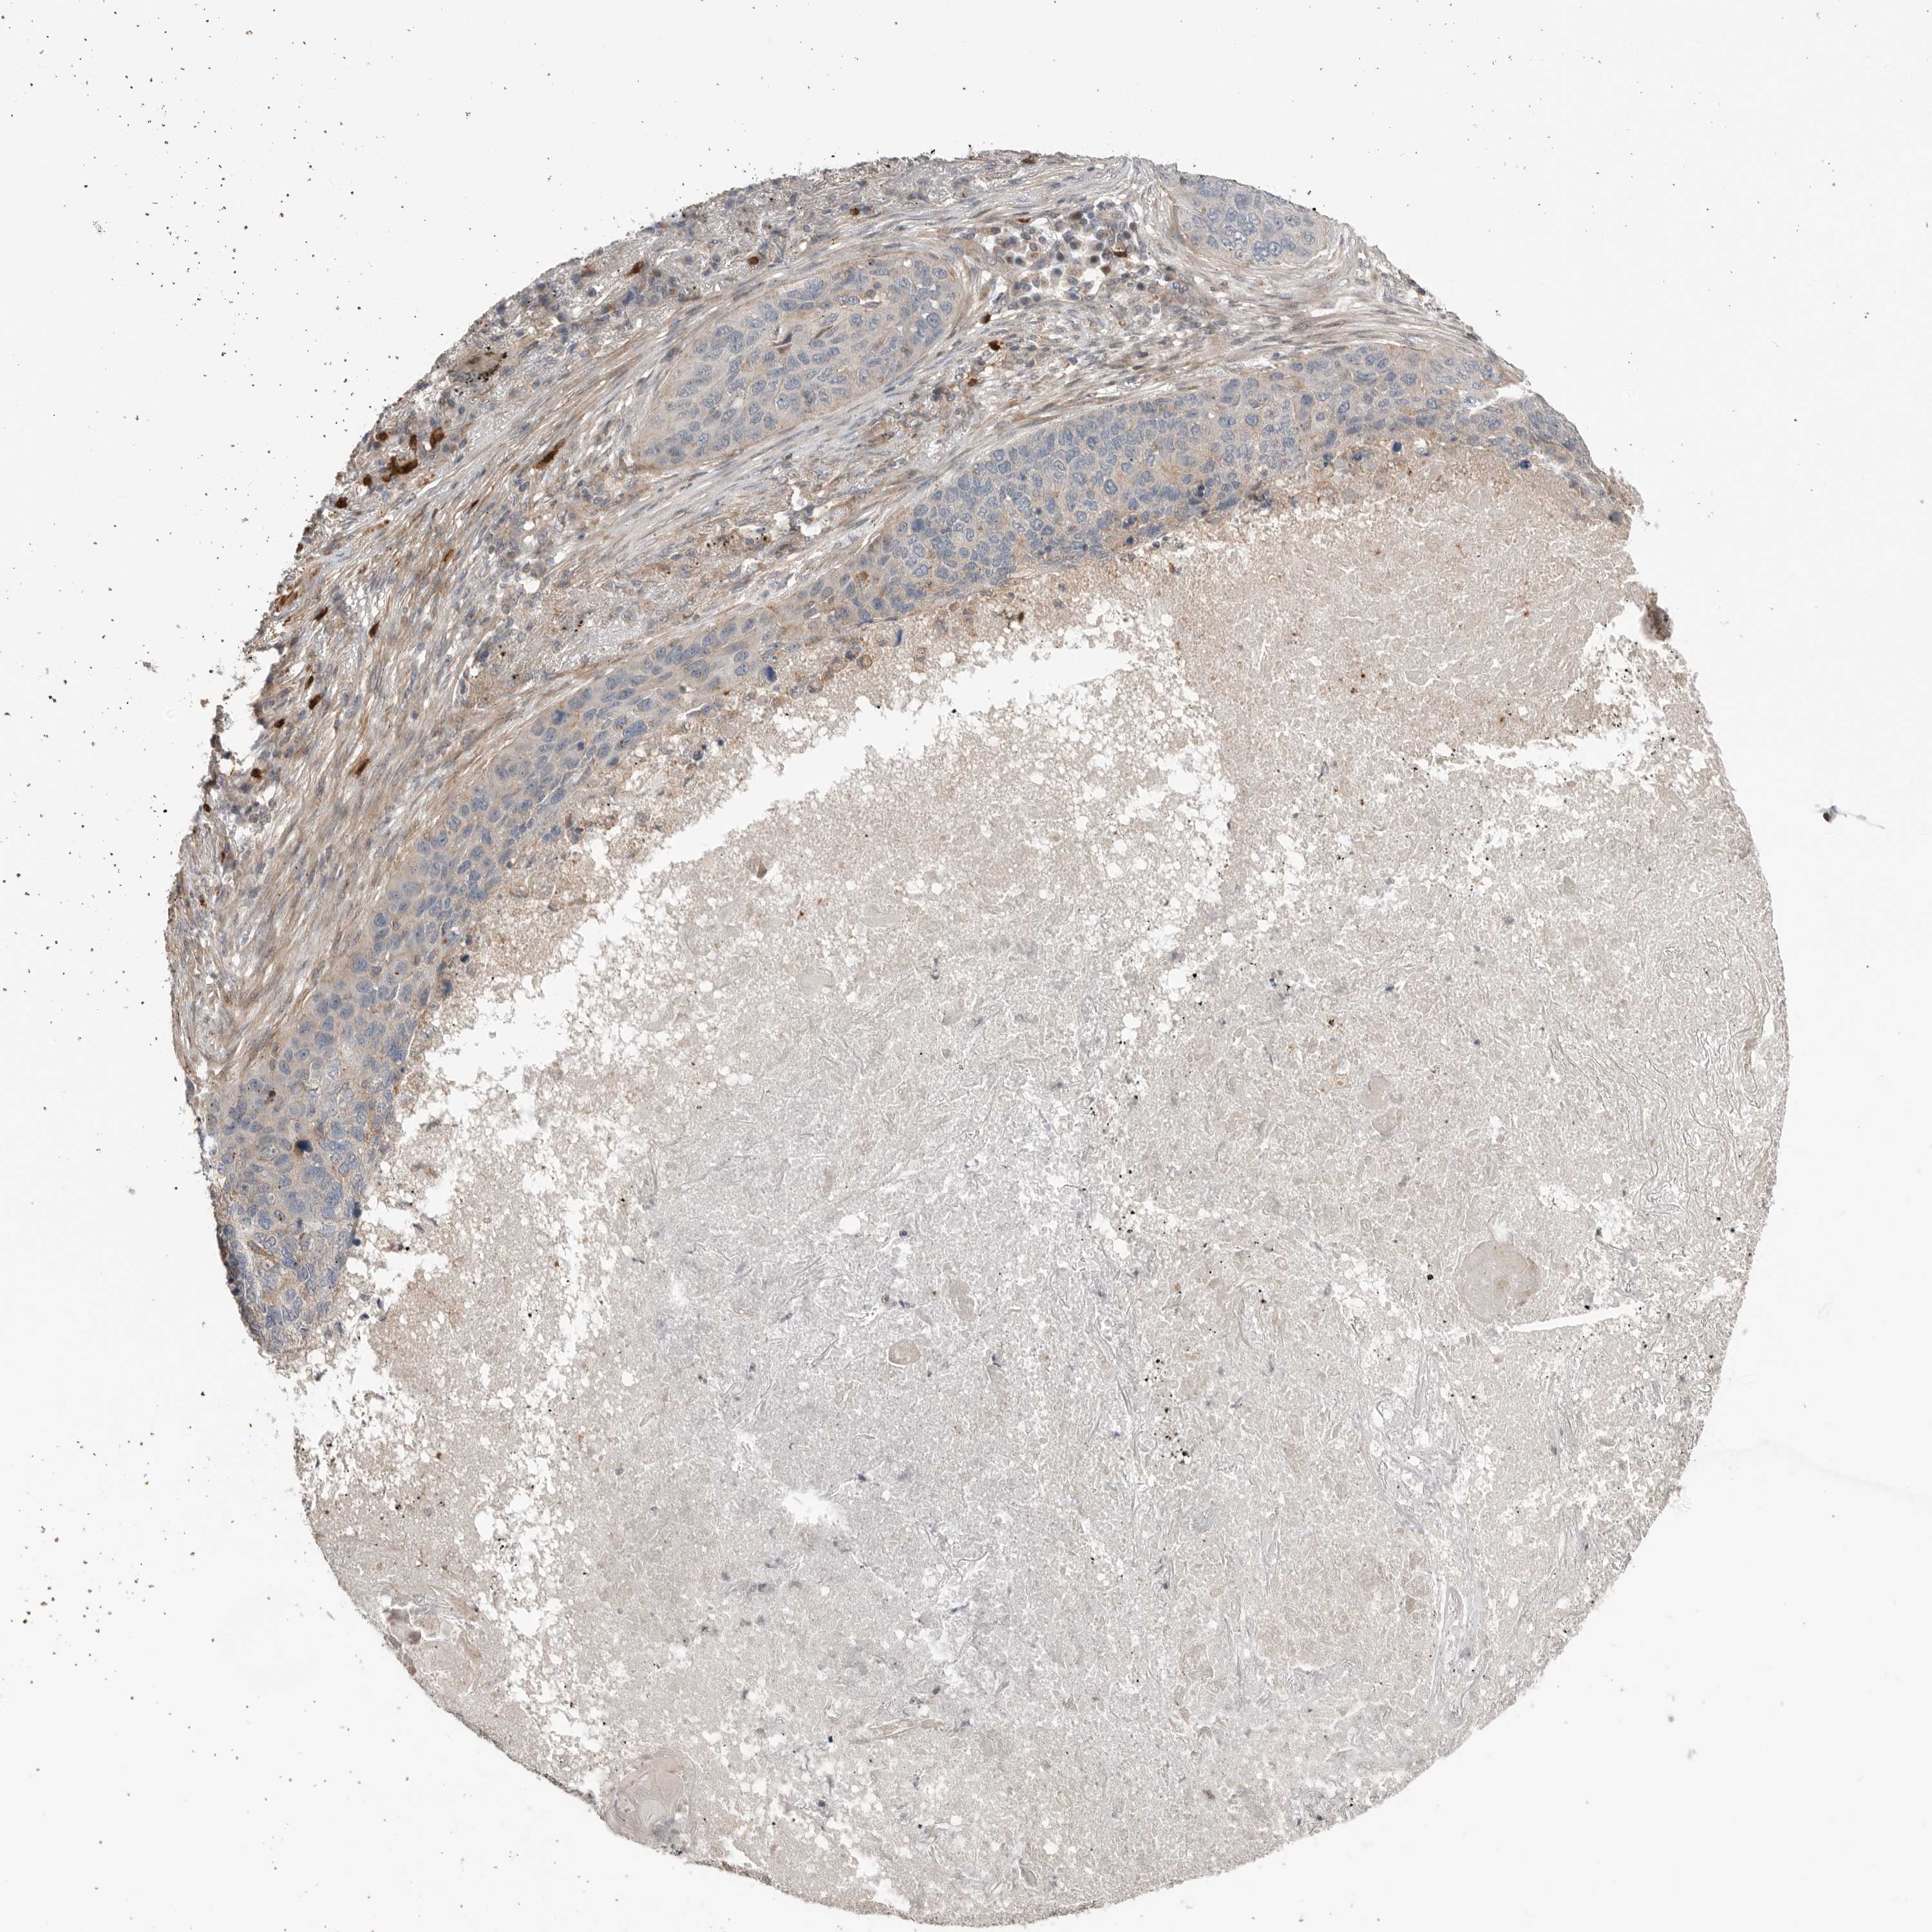

LUNG ADENOCARCINOMA (VALIDATION) - Interactive survival scatter ploti

The Survival Scatter plot shows the clinical status (i.e. dead or alive) for all individuals in the patient cohort, based on the same data that underlies the corresponding Kaplan-Meier plots. Patients that are alive at last time for follow-up are shown in blue and patients who have died during the study are shown in red.

The x-axis shows the expression levels (FPKM) of the investigated gene in the tumor tissue at the time of diagnosis. The y-axis shows the follow-up time after diagnosis (years). Both axes are complimented with kernel density curves demonstrating the data density over the axes. The top density plot shows the expression levels (FPKM) distribution among dead (red) and alive patients (blue). The right density plot shows the data density of the survived years of dead patients with high and low expression levels respectively, stratified using the cutoff indicated by the vertical dashed line through the Survival Scatter plot. This cutoff is automatically defined based on the FPKM cutoff that minimizes the p-score. The cutoff can be changed by dragging the vertical line or by entering a cutoff value in the square labeled "Current cut-off".

Under the Survival Scatter plot the p-score landscape (black curve; left axis) is shown together with dead median separation (red curve; right axis). Dead median separation is the difference in median mRNA expression between patients who have died with high and low expression, respectively. It is calculated as follows: median FPKM expression of dead patients with high expression - median FPKM expression of dead patients with low expression. This is intended to aid the user in visually exploring custom cutoffs and the associated p-scores and dead median separation.

Individual patient data is displayed and can be filtered by clicking on one or more of the category buttons on the top of the page. Categories describing expression level and patient information include: high, low, alive, dead, female, male and tumor stages. The scale of the x-axis can be toggled between linear and log-scale by clicking on the "x log" button. Mouse-over function shows TCGA ID, patient information and mRNA expression (FPKM) for each patient.

& Survival analysisi

Kaplan-Meier plots summarize results from analysis of correlation between mRNA expression level and patient survival. Patients were divided based on level of expression into one of the two groups "low" (under cut off) or "high" (over cut off). X-axis shows time for survival (years) and y-axis shows the probability of survival, where 1.0 corresponds to 100 percent.

PEAK1 is not prognostic in Lung Adenocarcinoma (validation)

Best expression cut offi

Based on the FPKM value of each gene, patients were classified into two groups and association between prognosis (survival) and gene expression (FPKM) was examined. The best expression cut-off refers the FPKM value that yields maximal difference with regard to survival between the two groups at the lowest log-rank P-value. Best expression cut-off was selected based on survival analysis .

When clicking on this number, the vertical dashed line indicating cut-off, the interactive survival plot, and the Kaplan-Meier curve will be adjusted to show results based on the best expression cut-off.

: 9.67

P scorei

Log-rank P value for Kaplan-Meier plot showing results from analysis of correlation between mRNA expression level and patient survival.

N/A

TCGA RNA samplesi

RNA-seq data is reported as average FPKM (number Fragments Per Kilobase of exon per Million reads), generated by the The Cancer Genome Atlas (TCGA) .

Normal distribution across the dataset is visualized with box plots, shown as median and 25th and 75th percentiles. Points are displayed as outliers if they are above or below 1.5 times the interquartile range. FPKM values of the individual samples are presented next to the box plot.

Average pTPM 10.0

Number of samples 105